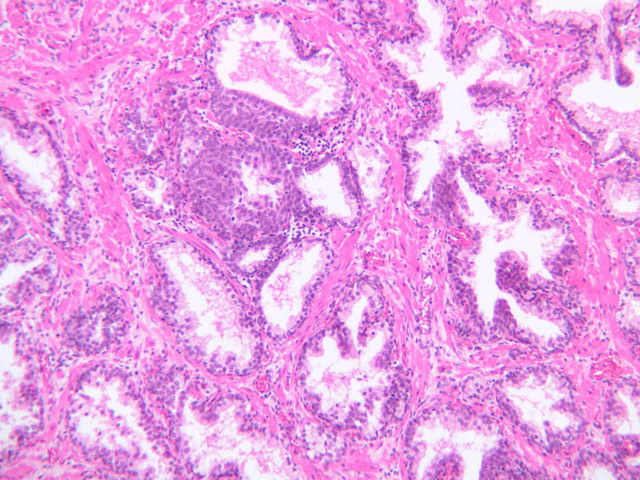

Scan a section of testis from the slide boxes at low magnification, and note the arrangement of the testicular components (slide B-80, H&E [1x-labeled, 1x, 1x]; B-81, PAS [1x, 1x]; B-82, adult monkey testis, H&E [1x, 1x, 1x, 1x, 1x] [2.5x, 10x]). A thick fibroelastic connective tissue capsule, or tunica albuginea, surrounds the testis. Within the tunica and sometimes bulging inward are a number of large blood vessels. The larger, thicker walled vascular profiles are sections through the testicular artery, which executes a highly convoluted course through the tunical plane. Closely applied to the outer surface of the tunica albuginea is the visceral layer of the tunica vaginalis, whose free surface is lined with mesothelium (B-81, PAS [2.5x-labeled]). In some specimens the parietal layer of the tunica vaginalis has been removed, but in others it is possible to find both layers of the tunica vaginalis and the potential serous space between them. How does the tunica vaginalis originate? Connective tissue septa extend inward from the tunica albuginea, subdividing the testis into a number of lobules. Within each lobule are numerous profiles of seminiferous tubules (B-82 [2.5x-labeled, 10x] [20x, 40x]). The interstitial space between the seminiferous tubules is occupied by a loose connective tissue matrix that is permeated by blood and lymphatic vessels and contains clusters of Leydig cells (interstitial cells) (B-82 [40x-labeled]).

Both androgens and spermatozoa are produced by the testis. Androgen synthesis is accomplished by Leydig cells. Leydig cells are often arranged in clusters with their distinct nuclei displaying a prominent nucleolus (B-82 [2.5x, 10x, 20x-labeled, 40x-labeled]). These clusters are located in close proximity to small blood vessels or elements of the extensively developed testicular lymphatic system. What might this relationship facilitate? The abundant eosinophilic cytoplasm usually has vacuolated appearance. Observe the interstices at high magnification in slide B-80 (H&E [2.5x, 10x, 20x, 40x-labeled] [10x, 20x, 40x]). Be aware, however, that most of the empty-appearing interstitial spaces in these slides are artifacts of specimen preparation.

Sperm production, or spermatogenesis, encompasses two distinct series of events: one affecting mostly the nucleus, the other affecting mostly the cytoplasm. First, there is a series of events, known collectively as spermatocytogenesis, in which rounded diploid stem cells (spermatagonia) give rise to clusters of rounded haploid cells (spermatids). Then there is a series of events, known collectively as spermiogenesis, in which the round spermatid spins a long flagellum, undergoes compaction of its nucleus, transforms its Golgi complex into an acrosomal cap, and sheds nearly all of its cytoplasm to yield a spermatazoa. Bear in mind that if you are to develop a good sense of the dynamics of sperm production, you will have to examine a number of seminiferous tubules. This is because spermatogenesis is typified by complex waves of proliferation and differentiation that sweep both around the circumference and along the length of the seminiferous tubule. Using the high dry objective, search slide B-81 for a transversely sectioned seminiferous tubule (i.e. one that presents a round profile in which a large lumen is surrounded by an epithelial wall of uniform thickness). Observe that the peripheral surface is demarcated by a continuous layer of small flattened cells containing elongated basophilic nuclei. These are contractile myoid cells (similar to the myoepithelial cells of other glands), which aid in propulsion of the luminal contents towards the excurrent duct system (B-81, testis, PAS [2.5x-labeled, 10x, 20x. 40x-labeled]; [10x, 20x, 40x]). The clearly stratified seminiferous epithelium differs in appearance from one tubular profile to another and even from one part of a single tubule to another. The seminiferous epithelium is composed of two populations of cells: proliferating cells of the germinal spermatogenic series and nonproliferating Sertoli cells. Sperm production begins with mitotic division of cells located at the tubule periphery; later events occur progressively closer to the lumen. In typical H&E preparations of seminiferous epithelium it is the distinctive qualities of nuclei that stand out against poorly defined cytoplasm (B-80, testis, H&E [20x, 40x-labeled] [10x, 20x, 40x-labeled] [10x, 20x, 40x] [2.5x, 10x, 20x, 40x]; B-82, testis, H&E [2.5x, 10x, 20x, 40x] [2.5x, 10x, 20x, 40x] [10x, 20x, 40x] [10x, 20x, 40x]). Thus, in your study of seminiferous epithelium, it is nuclear appearance that will enable you to distinguish the following cell types: